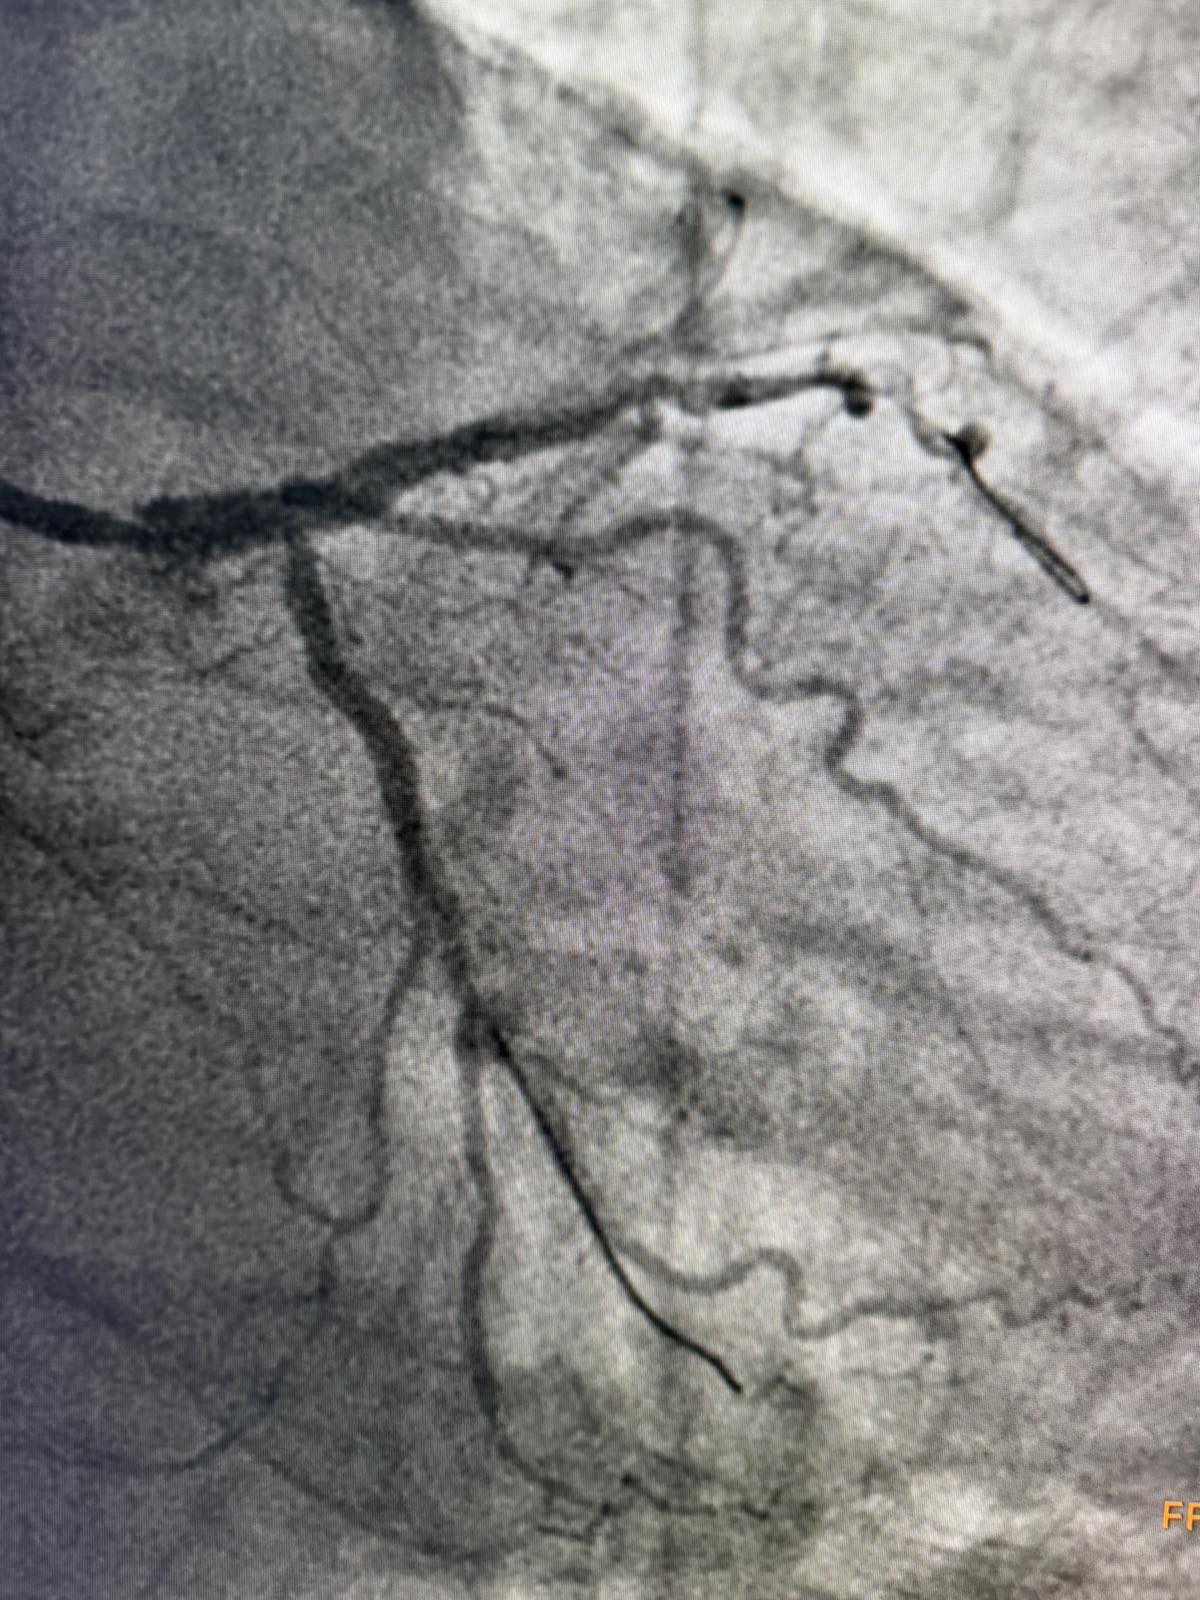

Tokom dva dana u angio sali izvedene su i izuzetno složene intervencije na koronarnim arterijama srca, uključujući perkutane intervencije na hronično - potpuno zapušenim krvnim sudovima srca i intervencije na tzv. glavnom stablu (left main) koja je glavna artrija srca i čije liječenje takođe spada u veoma rizične zahvate u interventnoj kardiologiji.

Još jedan slučaj koji izdvajamo kao posebno složen je bio kod pacijenta O.M (81), kod kojeg je dijagnostikovana teška trosudovna koronarna bolest.

„Pacijent je imao simptome angine pectoris. Nakon urađene koronarografije verifikovana je teška trosudovna koronarna bolest, gdje su bolesne bile desna koronarna arterija, dok je na lijevoj strani kritično mjesto bilo na glavnom stablu  odakle ide račvanje u dvije grane. Takvi pacijenti uglavnom završavaju na kardiohirurškom konzilijumu i na operaciji bajpasevima. Međutim, odluka konzilijuma u Banjaluci je bila da se, zbog godina života pacijenta,  radi perkutana intervencija na desnoj i lijevoj koronarnoj arteriji uključujući glavno stablo.Takve procedure zahtijevaju da se rade sa kontrolom imidžinga, savremene intravaskularne dijagnostike (IVUS), što smo mi i uradili. To dodatno povećava bezbijednost i preciznost zahvata. Procedura je trajala svega 45 minuta, a pacijent je već narednog dana otpušten kući“, izjavio je dr Janjičić.

Tim interventnih kardiologa JZU Bolnica „Sveti Vračevi“ Bijeljina je od 2020. godine izveo više od 100 intervencija na glavnom stablu (left main).